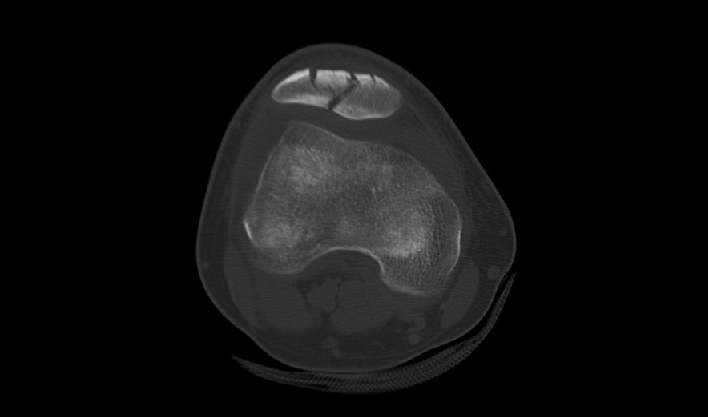

El detector de cuerpo ancho de cuarta generación, de desarrollo propio, cubre más áreas de tejido.

La matriz de reconstrucción de 1024*1024 amplía los datos de la imagen cuatro veces. Combinado con imágenes de corte fina, incluso las lesiones más invisibles son claramente visibles.